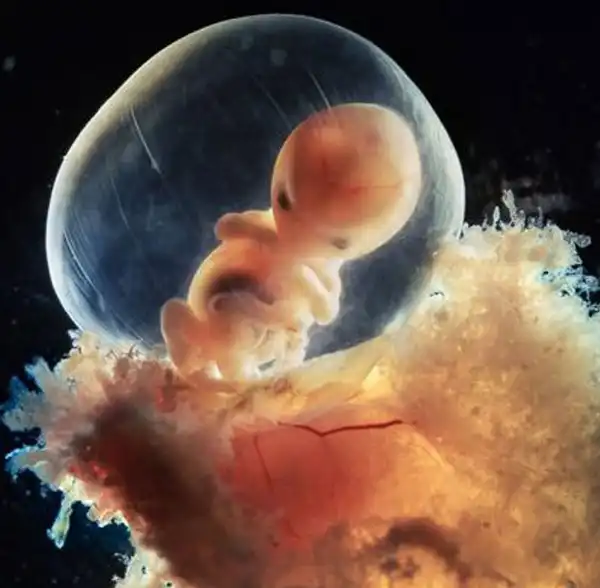

5 недель, длина 9 мм, уже угадывается лицо с отверстиями для рта, ноздрей и глаз

40 дней. Наружные клетки зародыша срослись с рыхлой поверхностью матки и образуют плаценту

8 недель